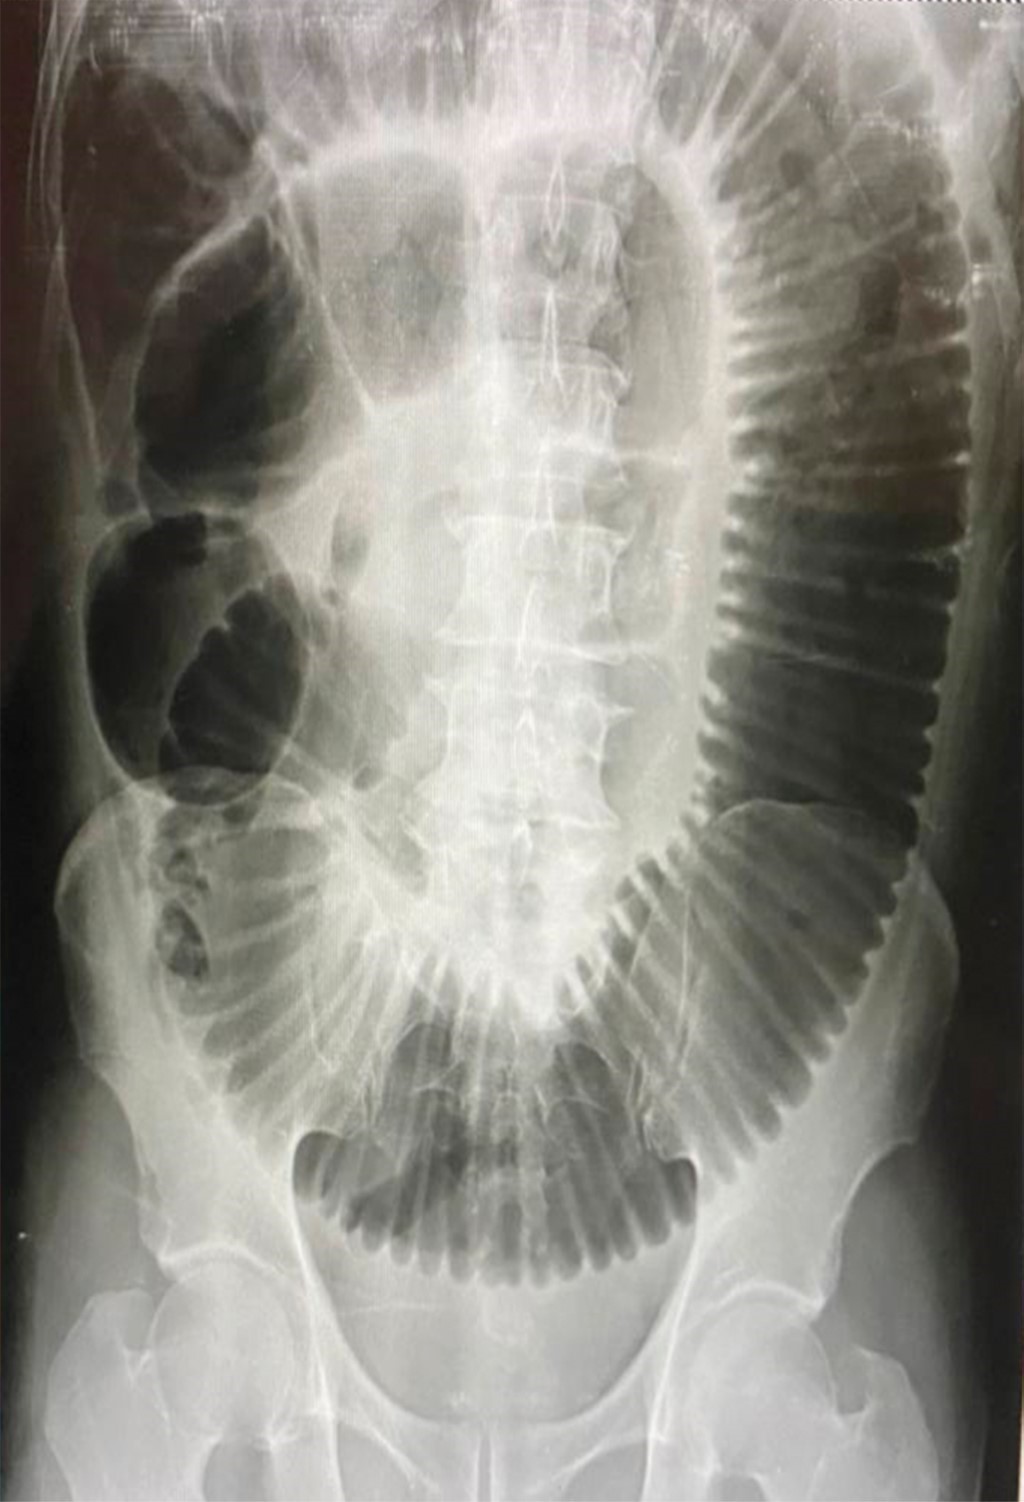

Los resultados de laboratorio se muestran en las Tablas 2, 3 y 4. La radiografía simple de abdomen en posición de pie muestra la presencia de distensión del intestino delgado, edema interasa con imagen en pila de monedas y niveles hidroaéreos, sin aire en colon (Figura 1). En la radiografía simple de abdomen en posición decúbito supino se aprecia el apilamiento de monedas y la presencia de imagen de burbujas duodenales (Figura 2).

Figura 2